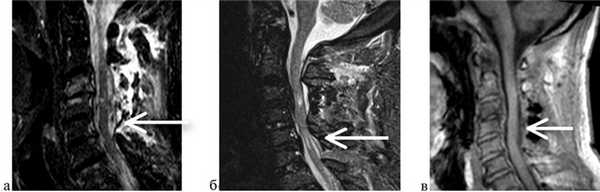

Сагиттальное сечение позвоночного канала после операции измерялось при помощи расчетной программы-локализера ClearCanvas Workstation 2.0. Переднезадний размер позвоночного канала был увеличен в среднем на 0,77±0,23 см (рис. 5 и 6). В трети случаев мы добились увеличения позвоночного канала более чем в 2 раза (рис. 7, 8).

Рис. 5. Расчет поперечного сечения до (а=0,91 см) и после операции (б=1,45 см). Сагиттальный и аксиальный срез на уровне С4—С5. а — грубая компрессия спинного мозга; б — спинной мозг декомпремирован, переднее и заднее субарахноидальное пространство просматривается полностью. Рис. 6. Расчет поперечного сечения до (а=0,84 см) и после операции (б=1,93 см). Сагиттальный и аксиальный срез на уровне С3—С4. а — грубая компрессия спинного мозга; б — спинной мозг декомпремирован, переднее и заднее субарахноидальное пространство просматривается полностью. Рис. 7. МРТ пациента Б. а — до операции. Определяется грубая компрессиия спинного мозга на уровне С2—С4, с формированием миелопатического очага. Полностью отсутствует визуализация переднего и заднего субарахноидальных пространств; б — после операции. Декомпрессия позволила визуализировать часть переднего и полностью заднее субарахноидальное пространства. Рис. 8. МРТ и МСКТ пациента Ш. а — грубая компрессия спинного мозга остеофитом на уровне С5—С6; б, в — МРТ и МСКТ после ламинопластики, несмотря на наличие остеофита подъем заднего комплекса создал полноценную декомпрессию спинного мозга.

У 1 (3,3%) пациента, с учетом данных дооперационных МРТ, выполнена ламинопластика С3—С4, С6. Был получен хороший послеоперационный исход, однако на контрольной МРТ отмечены нарастание выраженности компрессии на уровне С5 и появление клинической симптоматики (рис. 12). Поэтому первичное оперативное вмешательство позже было дополнено ламинопластикой С5.

Рис. 12. МРТ пациента П. а — МРТ до операции: стрелкой указана компрессия; б — МРТ того же пациента через 3 мес декомпрессии: стрелка указывает сохранение компрессии на уровне С5; в — МРТ после повторного вмешательства: компрессия ликвидирована.